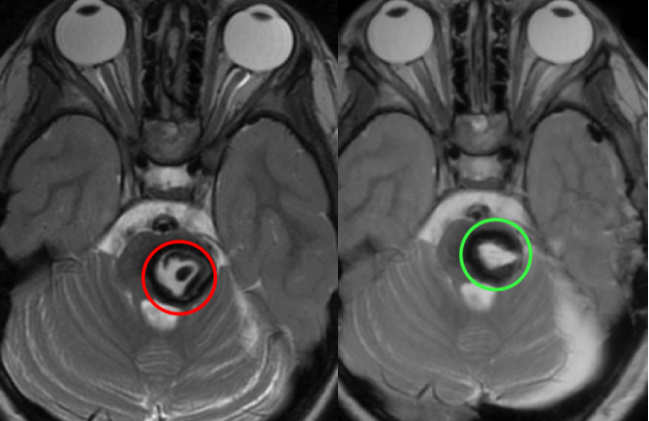

红色为术前,绿色为术后即刻颅脑MR影像,显示病变已全切,无脑水肿、出血等并发症,瘤腔内高信号灶为止血材料。